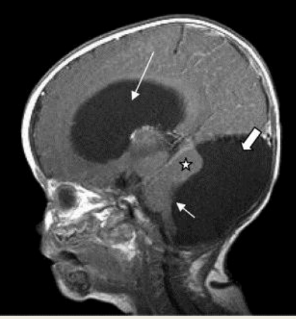

14

Q

MRI shows enlarged 4th ventricles and cerebellar hypoplasia, as well as enlargement at the base of the skull in the posterior fossa. What disease process is this?

A

Congenital brain malformation

Dandy Walker Malformation

15

What is this?